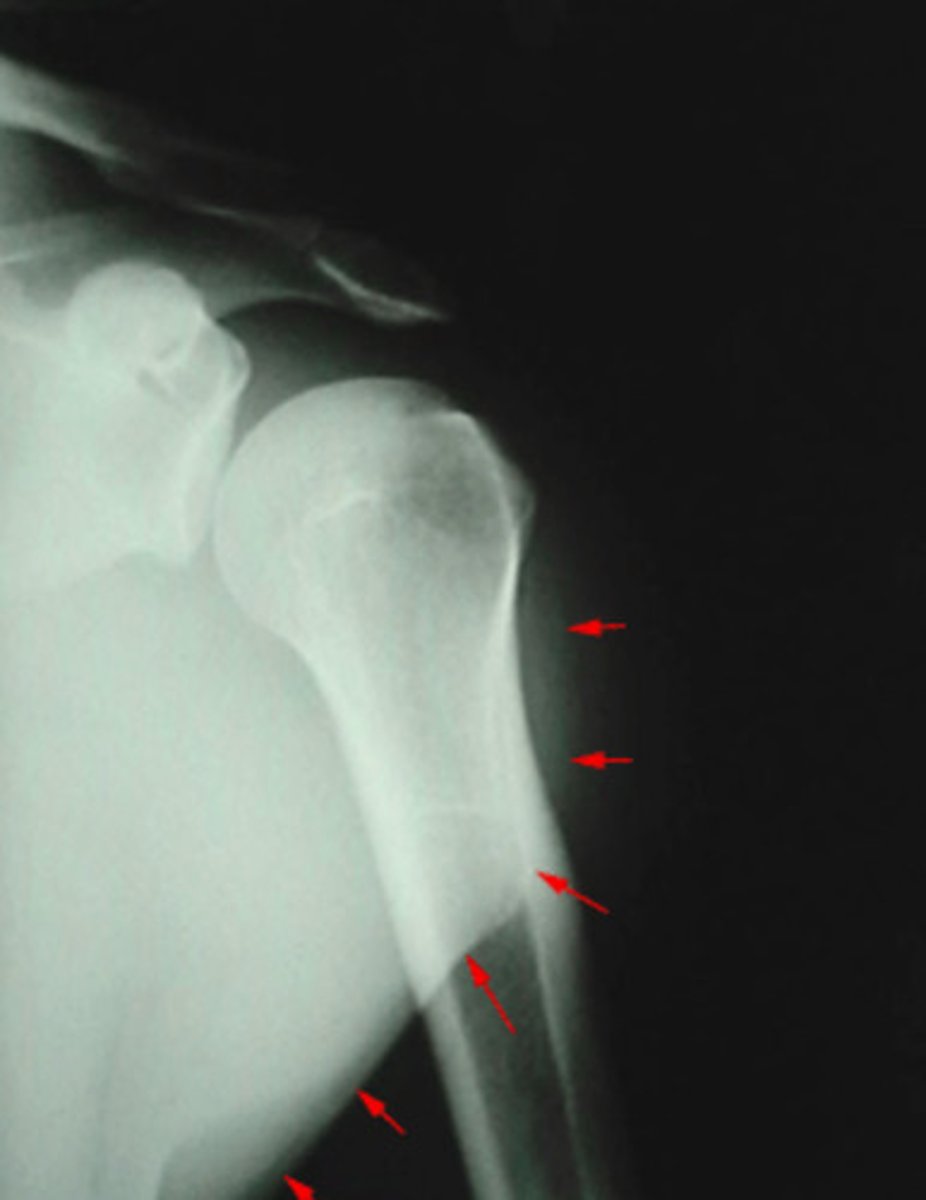

Soft tissue

What is being pointed out by the arrows in this image?